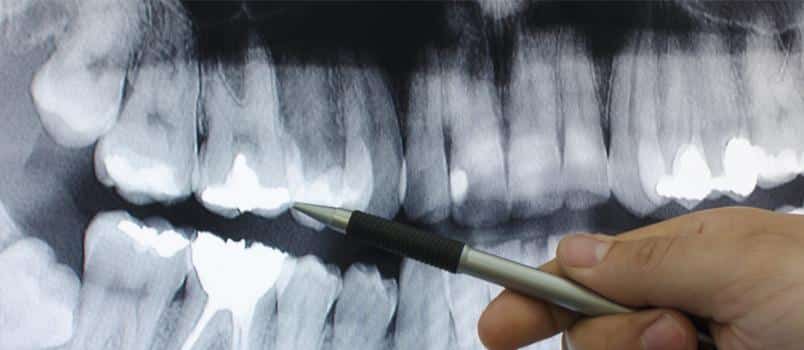

Screening x-rays help us see areas of your mouth that would otherwise not be seen in a routine physical examination. Because there are parts of your teeth and gums that are blocked from view, screening x-rays allow us to go deeper into those areas without having to cause any discomfort to our patient.

As soon as your screening is done, we study the results and learn important clues about your dental health such as tooth growth patterns and unseen areas of the tooth that may be damaged by tooth decay. We then come up with a proper dental treatment plan for you based on the findings of your physical examination and x-ray screening.

Screening x-rays are also important in preventing dental problems from worsening. A small crack in the tooth, for example, can be seen in x-ray results and can be corrected before it causes serious damage to your oral health.